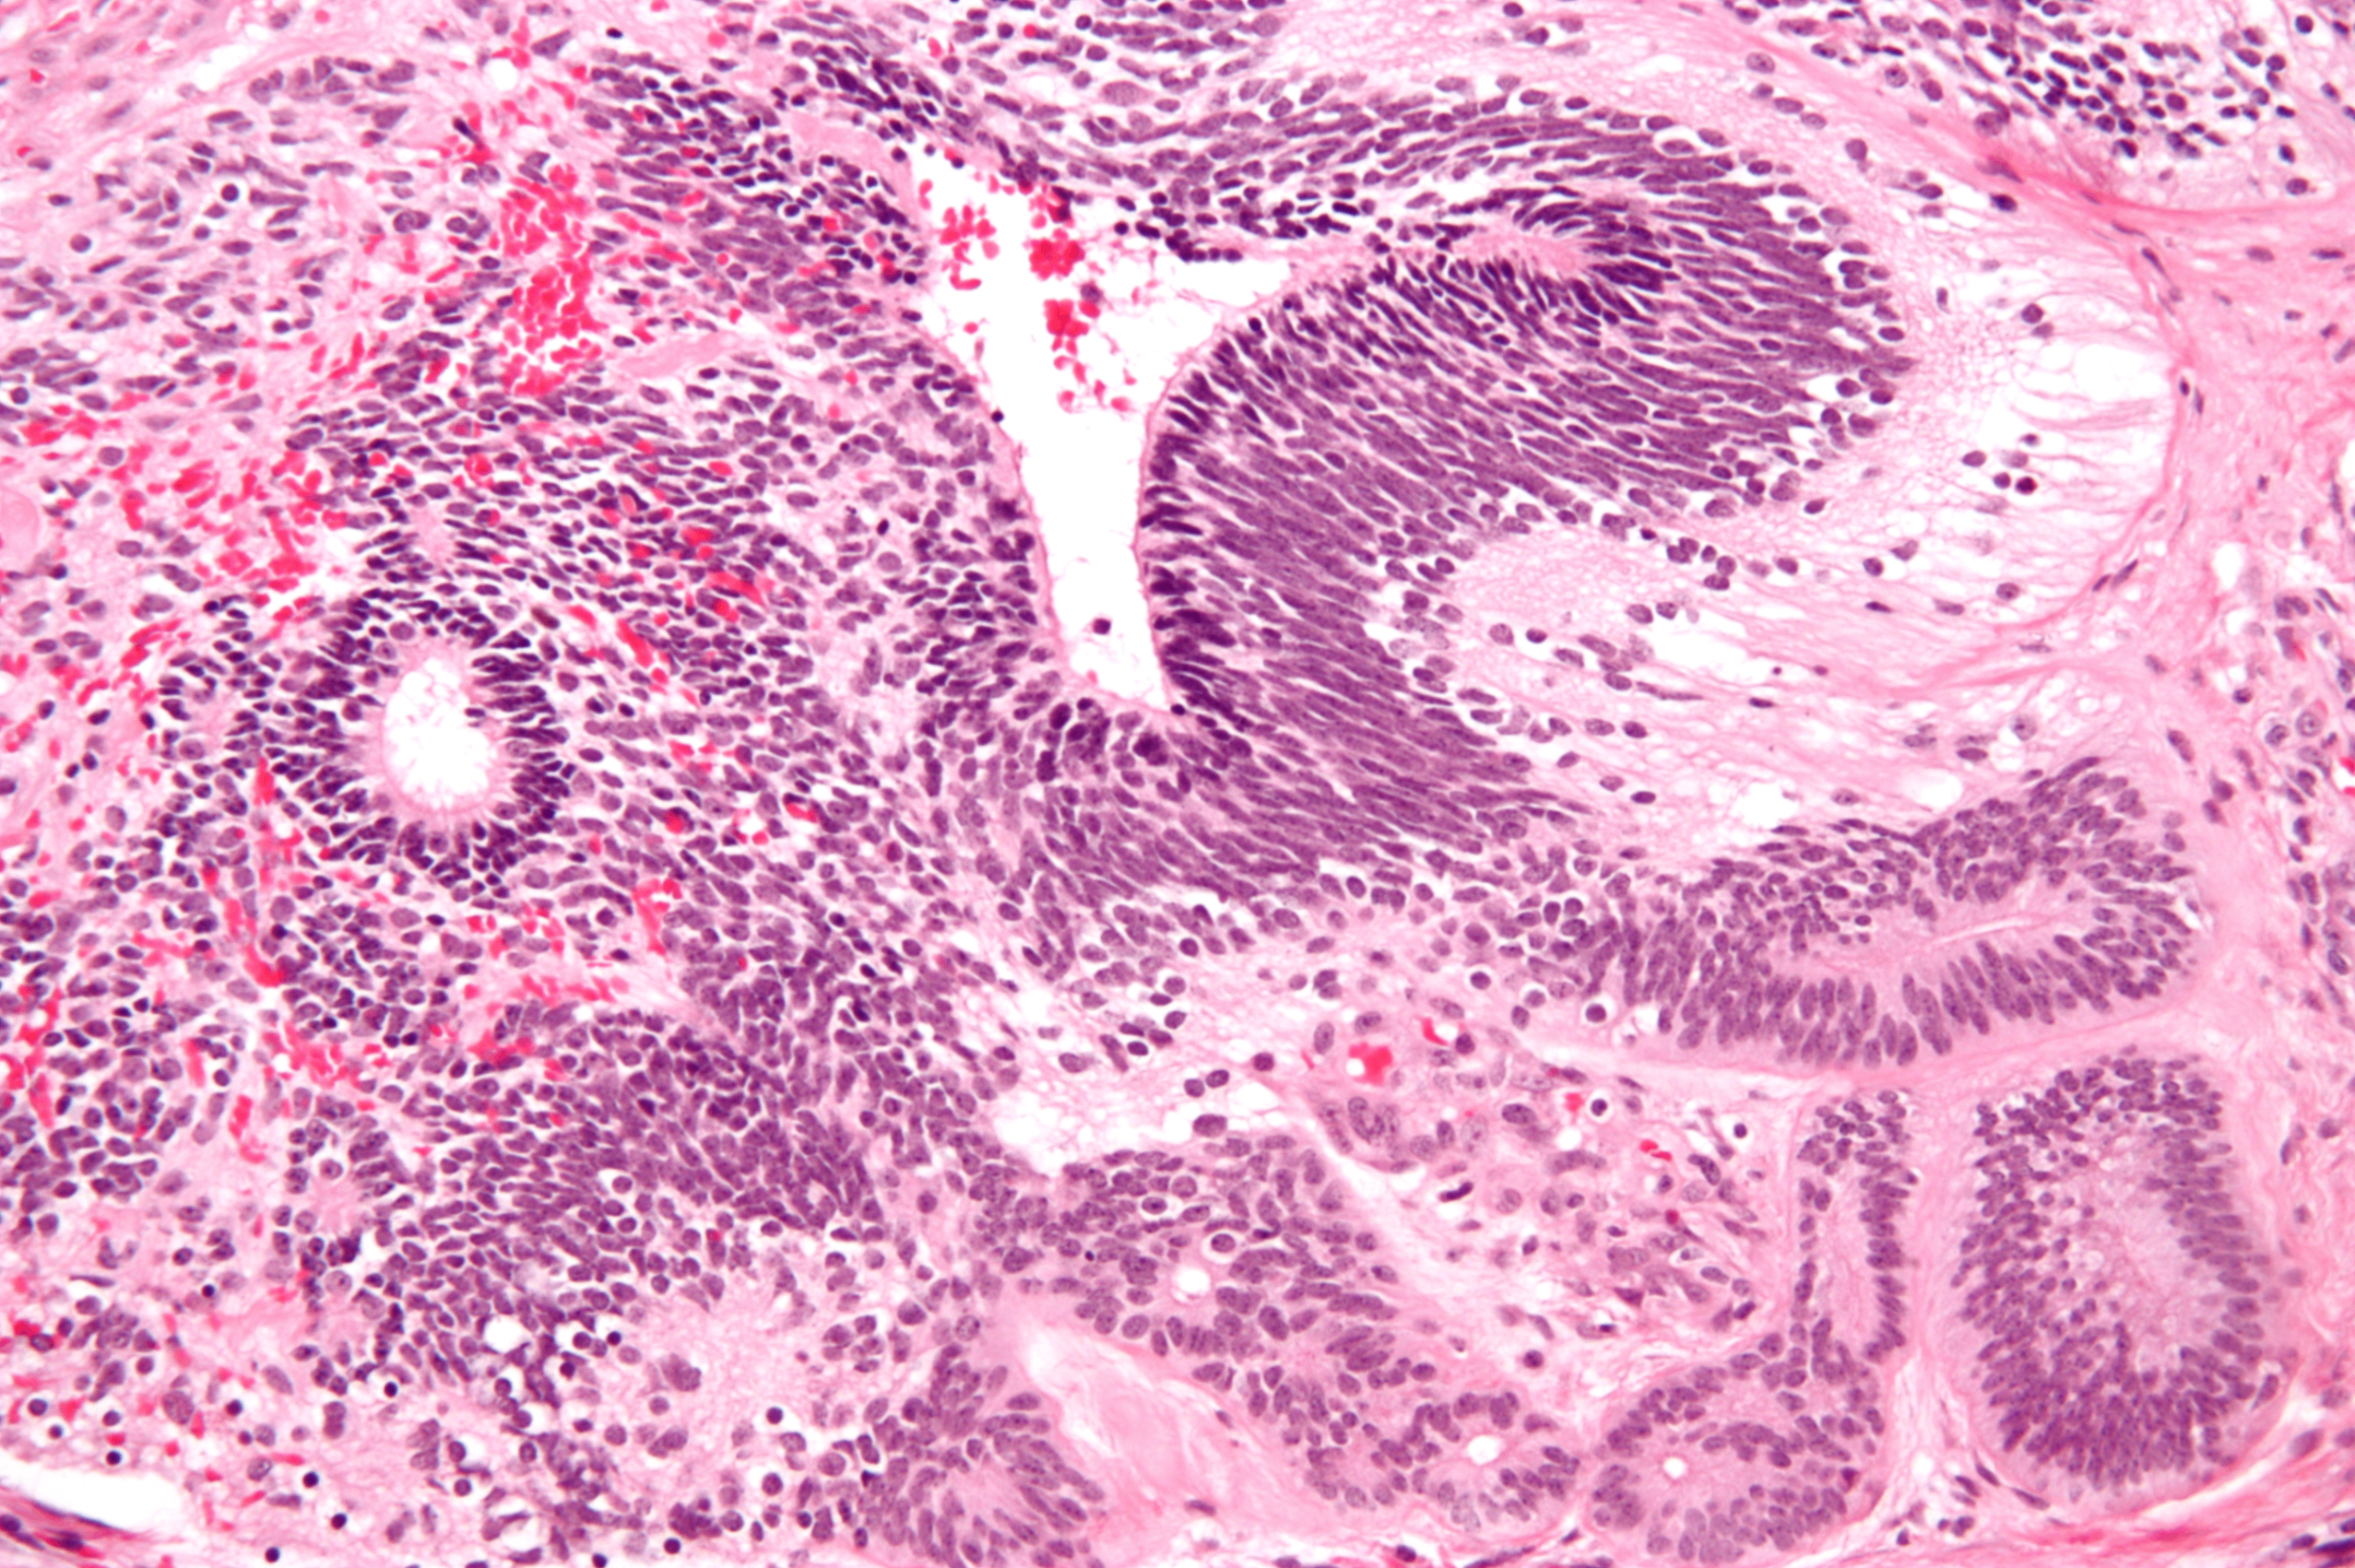

2) 병리학적 특징

a-fetoprotein (aFP) 생성

대표적인 소견으로 Schiller-Duval body가 관찰됨; 이는 중심부의 혈관을 종양세포가 둘러싸 사구체와 유사한 모습을 지님

세포 내 hyaline droplet이 관찰되며 aFP에 대해 양성

Yolk sac tumor, Wikimedia Commons